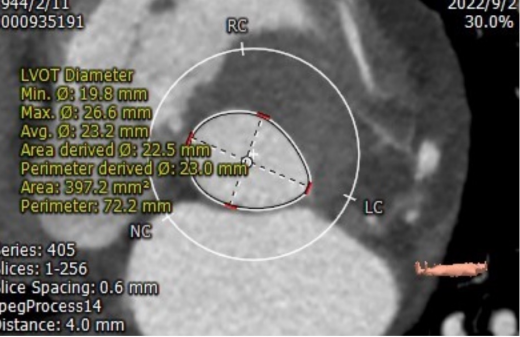

CT评估

1.瓣环及左室流出道

收缩期瓣环:70.3mm

收缩期流出道:72.2mm

舒张期瓣环:68.1mm

舒张期流出道:73.1mm

左冠高度10.8mm

右冠高度14.1mm

主动脉窦宽:32.8mm、31.3mm、32.4mm

窦管结合部:113.9mm

升主动脉:146.6mm